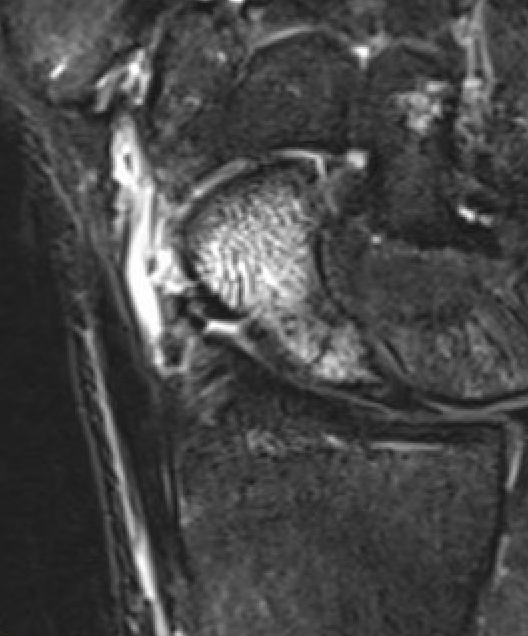

MRI

Indications

- occult fractures

- diagnosis of AVN

Occult scaphoid fracture on MRI

- 67 patients with normal xray and suspected scaphoid fracture

- 10% had scaphoid fracture on MRI

Dean et al Bone Joint Open 2021

- 258 patients with normal xray and suspected scaphoid fracture

- 13% had scaphoid fracture on MRI, 6% scaphoid contusion